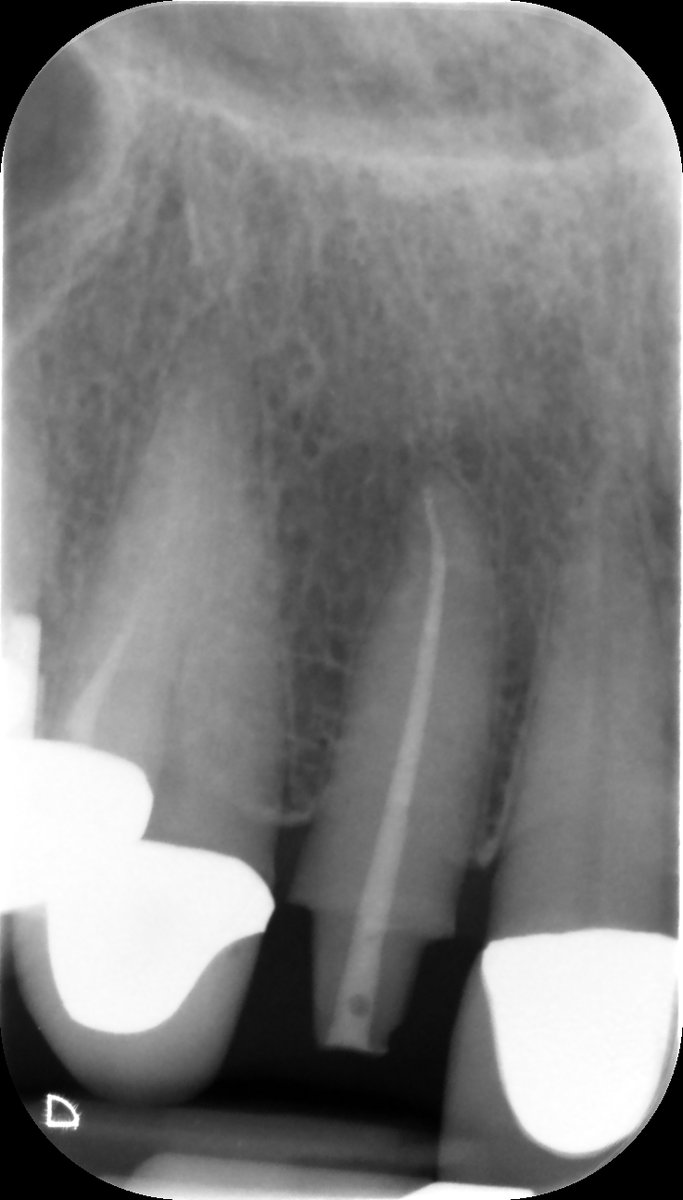

Happy Days in Endoland Saturday Surgery and saving teeth 🤣 UR6 referred for endo after difficulty finding canals. 5 canals in total, EdgeOne Fire preps. Onlay required. Review in 9 months. #savingteeth #endodontics